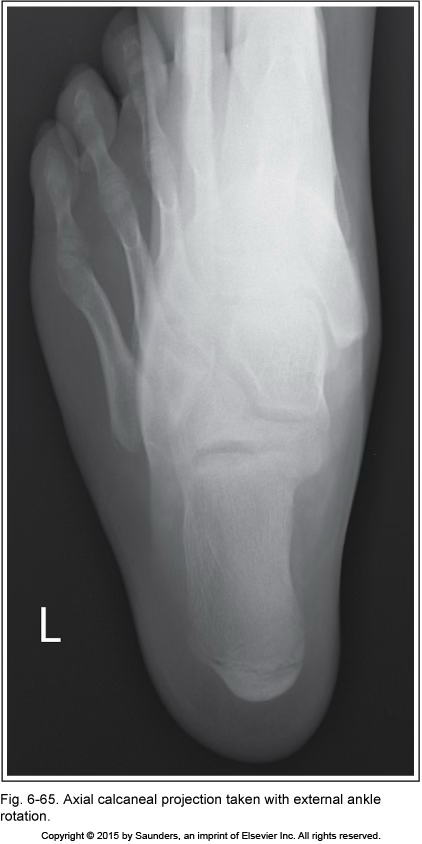

axial calcaneus

external ankle rotation

we see too much of toes